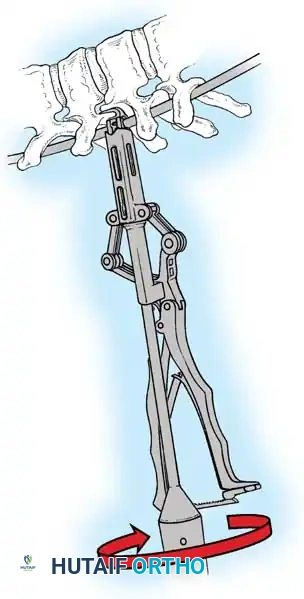

Fig. 38-22: Patient positioning on a Jackson table with hips in extension to maintain physiological lumbar lordosis.

Positioning on the Jackson Table

- Prone Positioning: The patient is carefully rolled prone onto an open-frame Jackson table (e.g., Mizuho OSI, Union City, Calif). The open frame is paramount as it allows the abdomen to hang free.

- Hemodynamic Optimization: Eliminating intra-abdominal pressure prevents compression of the inferior vena cava. This directly reduces venous engorgement within Batson’s epidural venous plexus, drastically minimizing intraoperative blood loss during exposure and pedicle cannulation.

Surgical Warning: When a patient is positioned prone with the hips flexed, physiological lumbar lordosis is artificially obliterated. If the planned fusion extends into the lower lumbar spine (L3, L4, or L5), it is imperative to elevate the knees and thighs so the hip joints are fully extended. This maneuver restores and locks in normal lumbar lordosis, which is critical for preventing postoperative flatback syndrome and adjacent segment disease.